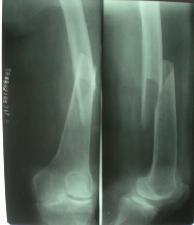

足跟可極度腫脹,踝後溝變淺,整個後足部腫脹壓痛,易被誤診為扭傷。X線檢查,除攝側位片外,應拍跟骨軸位像,以確定骨折類型及嚴重程度。此外,跟骨屬海綿質骨,壓縮後常無清晰的骨折線,有時不易分辨,常須依據骨的外形改變,結節-關節角的測量,來分析骨折的嚴重程度。

病人有典型的外傷史,患足承重困難和足跟疼痛,局部觸痛、腫脹和皮下淤血斑亦多明顯。在較嚴重的壓縮骨折時,除可見到足後跟的高度變低和足跟橫徑變寬以及外踝下部正常凹陷消失外,距下關節話動亦完全喪失。但跟骨周邊骨折僅有局部腫脹及壓痛,而距下關節活動範圍多屬正常。x線正、側、軸位片可明確跟骨的結節關節角和其橫徑寬度的改變。

影像學表現:(1)跟骨前突骨折。(2)跟骨結節的垂直骨折。(3)載距突骨折。(4)跟骨壓縮性骨折。(5)跟骨粉碎性骨折。

舌型骨折:跟骨骨折的舌型(tongue type)骨折:多系垂直暴力所致。 X線平片(包括正、側位及跟骨軸線位片)一般即可明確診斷,診斷困難者可行CT掃描或MRI檢查,尤其是CT掃描在該骨折分型診斷及預後判定上作用較大。